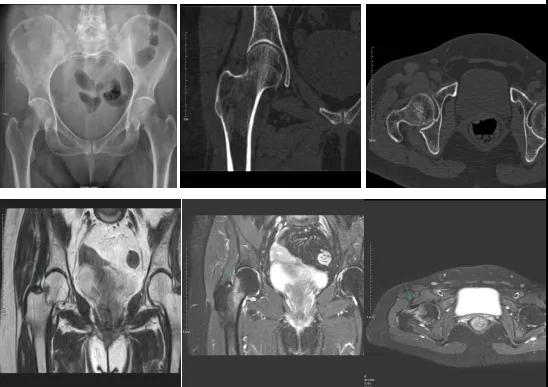

2.CT或MRI檢查。CT是斷面成像,不會(huì)出現(xiàn)重疊而導(dǎo)致漏診,同時(shí)CT還可以進(jìn)行多平面的重建,除了發(fā)現(xiàn)X線無法發(fā)現(xiàn)的骨折外,還可以三維直觀的顯示骨折的程度,對臨床治療有指導(dǎo)意義。CT無法發(fā)現(xiàn)骨裂、不全骨折或者骨挫傷,對軟組織的損傷診斷也有局限性,MRI就可以發(fā)現(xiàn)這些損傷。

DR示:右側(cè)股骨頸未見明顯骨折征象。CT右側(cè)股骨頸骨質(zhì)密度不均?;颊唧w征明顯,為明確診斷,行MRI檢查。MRI示:右側(cè)股骨頸T1WI呈低信號,脂肪抑制序列呈高信號;提示右側(cè)股骨頸隱匿性骨折。